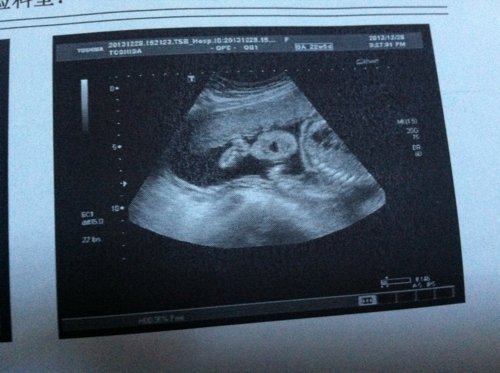

这是今天检查的三围彩超…现在怀孕23周这样…不知道怎么样…昨晚开始左胸开始闷…心脏也不舒服…怎么谁

这是今天检查的三围彩超…现在怀孕23周这样…不知道怎么样…昨晚开始左胸开始闷…心脏也不舒服…怎么谁都不舒服…左侧睡感觉把心脏压的不舒服…可是右侧睡也不舒服…左胸闷

病情分析: 可去正规医院做好孕产期保健,严密观察胎儿发育.建议你在孕15-20周做唐氏筛查看胎儿的智力发育情况, 指导意见: 在孕22-26周内做四维彩超排畸检查了解胎儿有无大体畸形及主要器官发育情况为好。